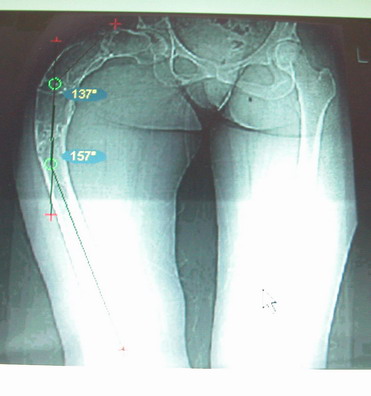

Моё мнение, что двойная остеотомия бедра с аппаратом Илизарова + Гексаподный механизм, или Тэйлора, В данной ситуации является методом выбора. Я очень извеняюсь за качество прилагаемых снимков, в которых я постарался отразить разницу междe одной и двумя остеотомиями бедра.